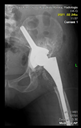

The guiding wire was inserted and controlled with fluoroscopy flashes (Figure 4). The drilling and reaming were carried out in accordance with the recommendations:

Figure 4.

The biocompatible aiming device after insertion of the guiding wire.

The direction of the cup stem was determined by the guide wire. The aiming device was needed to introduce this wire. After removing the aiming device, the next step was the drilling. Since a cannulated drill bit was used, the previously installed wire could guide the process. A self-positioning reaming tool was then used in the drilled channel. In the prepared cavity, the cup was fitted perfectly. Of the two stemmed cups available to us, the McMinn cup (Waldemar Link, Hamburg, Germany) had the simpler geometry and was therefore chosen. The stemmed cup was inserted according to the manufacturer’s recommendation. In the presence of a significant bone defect, a synthetic bone graft may be impacted for substitution.

In all the cases operated with the above-described targeting procedure, the stems of the cups remained between the cortical bone surfaces without perforation of the linea terminalis, as shown by postoperative radiographs. There were no complicated surgical situations. In 16 cases, the wound healings were uneventful, and the hips were able to bear weight again after postoperative rehabilitation.